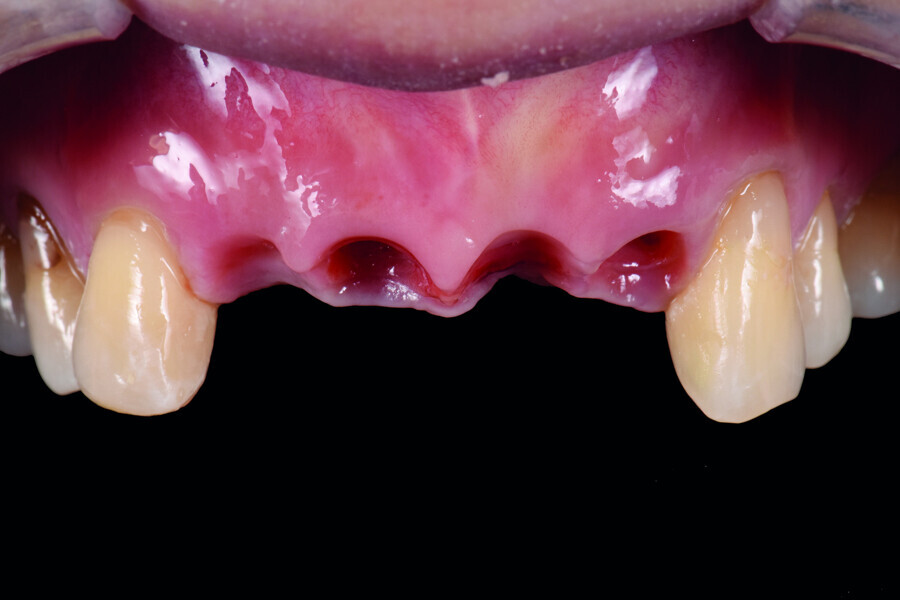

Fig. 5: Frontal view of the anterior teeth immediately post-op.

Fig. 6: Occlusal view of the anterior teeth immediately post-op.